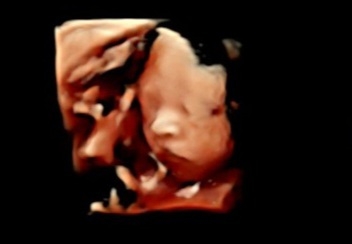

입체초음파 드디어 성공😊

입초볼때마다 뒤돌아버리거나 두손으로 가리거나 탯줄로 가려서 매번 실패했는데 드디어 성공했어요ㅠㅠ❣️❣️ 매번 오후에 가다가 오전에 가니 얼굴을 이렇게나 잘보여주네요ㅎㅎ

꺄~콧대 너무 오똑한대용!!

감사합니다😊 얼굴제대로보는것도 처음인데 콧대도 있어서 뿌듯해하는중이에요ㅎㅎ